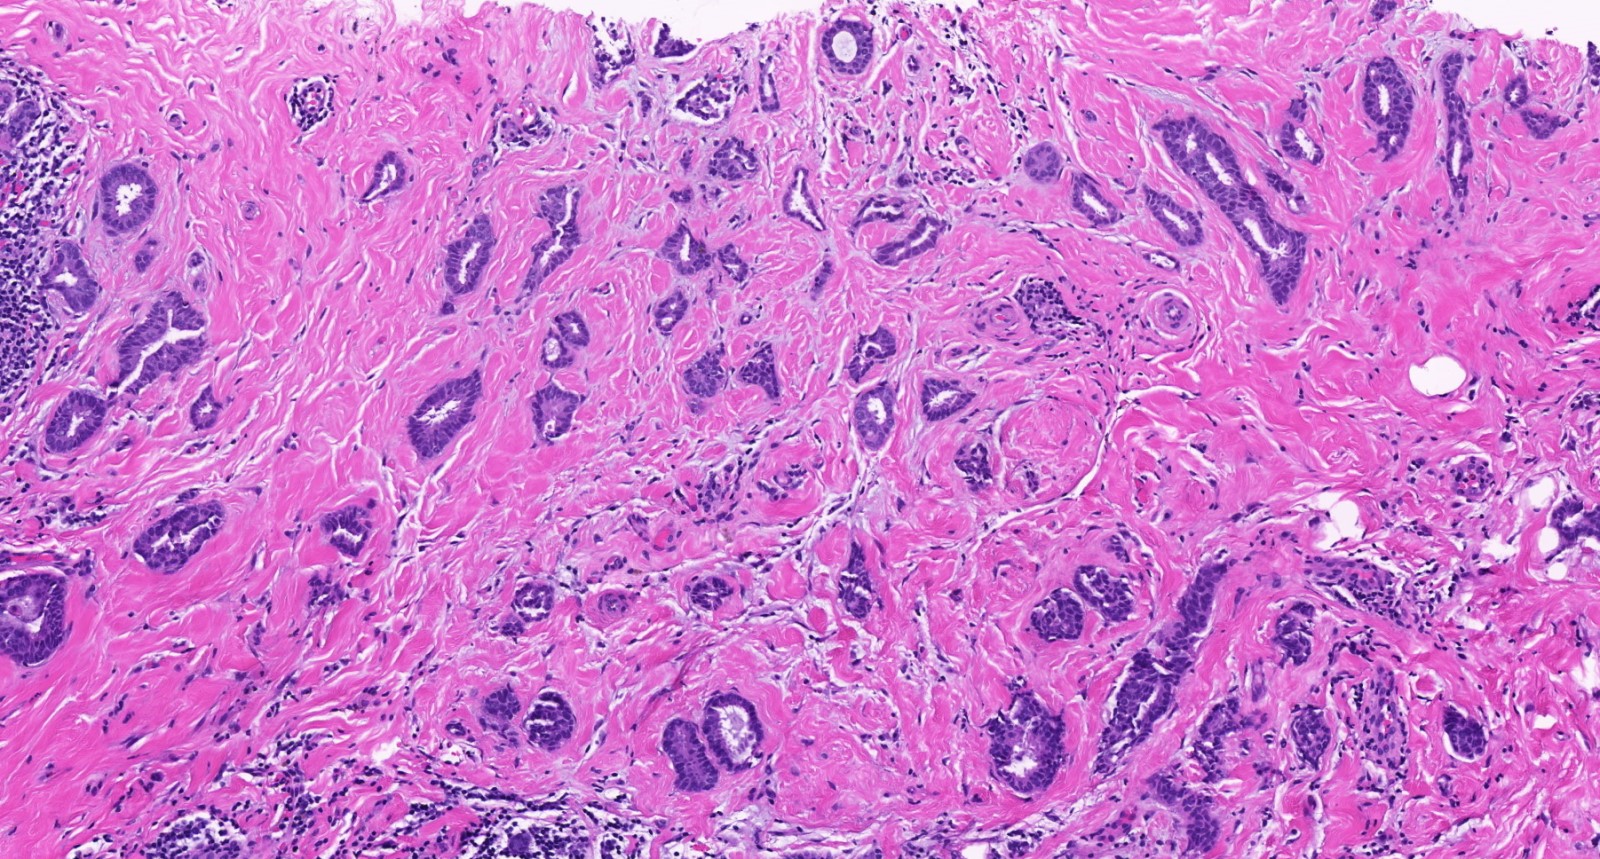

Microscopic (histologic) description

- Histologic grading is based on the Nottingham / modified Bloom & Richardson Score (Histopathology 1991;19:403):

- Tubule formation (1 - 3 points):

- > 75% (1 point)

- 10 - 75% (2 points)

- < 10% (3 points)

- Nuclear pleomorphism (1 - 3 points):

- Small, regular, uniform, similar to normal ductal epithelial cells, 2 - 3x RBC (1 point)

- Moderate increase in size / variability (2 points)

- Large nuclei, marked variation, often vesicular chromatin with prominent nucleoli (3 points)

- Mitotic count (1 - 3 points), dependent on microscopic field area

- Total score (add points for tubule formation, nuclear pleomorphism and mitotic count):

- 3 - 5 points: grade 1

- 6 - 7 points: grade 2

- 8 - 9 points: grade 3

- Histological features of IBC NST vary considerably from case to case and even within the same case

- Margins vary from highly infiltrative, permeating the surrounding tissue, to continuous pushing margins

- Architecture varies from sheets, nests, clusters, cords or individual cells (but lacks the cytomorphological characteristics of invasive lobular carcinoma)

- Tubular formations are prominent in well differentiated tumors but absent in poorly differentiated tumors

- Variable cytological features:

- Cytoplasm may be abundant and eosinophilic but it can show other features in some tumors, including as clear, foamy or granular

- Nuclei may be regular and uniform or highly pleomorphic with prominent or multiple nucleoli

- Mitotic figures are variable from virtually absent to extensive

- 2 distinct growth patterns exist:

- Large and solid nests or syncytial infiltrative growth pattern with little associated stroma and an expansive growth that compresses the surrounding stroma (e.g., most basal-like breast cancers)

- Tumors characterized by small cancer nests accompanied by marked fibrosis (desmoplastic / scirrhous); this type diffusely infiltrates the surrounding tissue as an irregular shaped spiculated mass

- Calcification in 60% of cases, variable necrosis

- Elastosis involves stroma, wall of vessels and ducts and causes grossly noted chalky streaks

- Often ductal carcinoma in situ (DCIS) (up to 80%)

- In some cases, DCIS is extensive

- Associated DCIS is usually of same nuclear grade as the invasive carcinoma

- Perineural invasion (28%)

- Mast cells are associated with low grade tumors

- Uncommon features: eosinophils intraluminal crystalloids (BMC Cancer 2007;7:165, Arch Pathol Lab Med 1997;121:593)

- No myoepithelial cell lining (as seen in DCIS or benign lesions)

- Angiolymphatic invasion in 35%; differs from tissue retraction because:

- Occurs outside margin of carcinoma

- Does not conform precisely to space it is in

- Endothelial lining is present and is CD31+, ERG, D2-40+, CD34+ and factor VIII+

Microscopic (histologic) images

Contributed by Julie M. Jorns, M.D., Kristen E. Muller, D.O., Gary Tozbikian, M.D. and Emad Rakha, M.D.